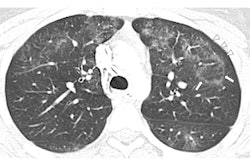

Using the telecritical care service, the researchers tracked 60 EVALI cases identified within the health network between June 27 and October 4, 2019. They defined EVALI as a clinical diagnosis based on the identification of pulmonary infiltrates on chest x-ray or CT within 90 days of electronic cigarette (e-cigarette) use and the absence of another known illness.

Overall, the group found that EVALI was associated with severe lung injury on radiological imaging and also general constitutional and gastrointestinal symptoms in nearly all the cases. Highlights from their observations of the EVALI cases included the following:

Of note, two patients originally presented with vague abdominal symptoms and were referred to the EVALI task force only after CT scans revealed bilateral ground-glass opacities in the lung bases.

The chest x-ray of a patient with vaping-associated lung injury shows lung opacities, densities, and whitish cloud-like areas common in unusual pneumonias, pulmonary edema, and lung inflammation. Image courtesy of Intermountain Healthcare.These findings are helping physicians recognize what lung injuries associated with e-cigarettes or vaping look like -- and helping them maintain a high degree of suspicion when they diagnose lung injuries in patients who've been vaping, Blagev noted.